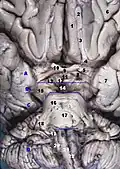

Корональный срез головного мозга через промежуточную массу третьего желудочка

- Головной мозг. Глубокое рассечение. Нижняя диссекция

- Ножка мозга, щель зрительного нерва, водопровод мозга. Низкий вид. Глубокое рассечение

- Головной мозг. Вид снизу. Глубокая диссекция

- Головной мозг. Нижний вид. Глубокое рассечение